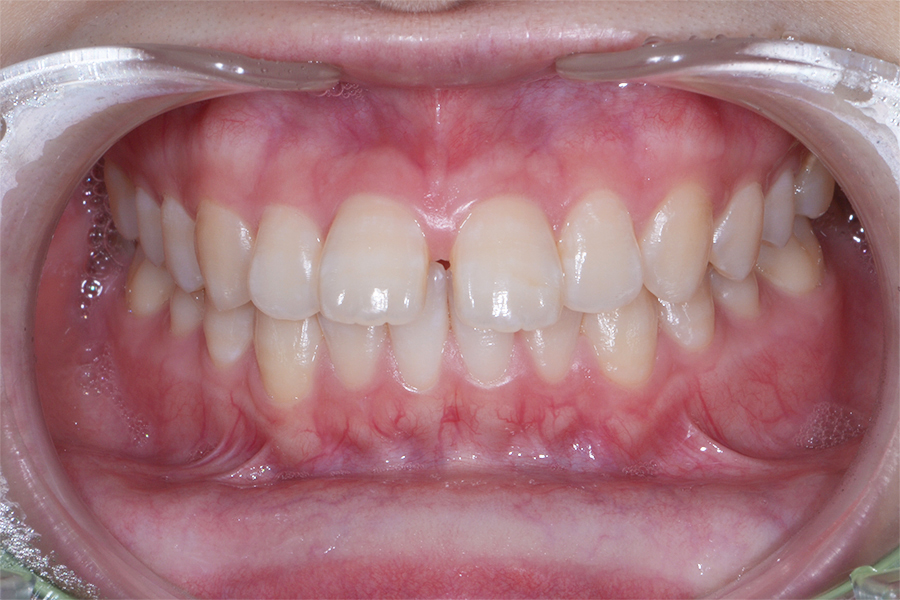

【20代女性】

真ん中二本のねじれを

引っ込めたい

【矯正歯科治療】

- 担当医

- 三留先生

- 主訴

- 真ん中二本のねじれを引っ込めたい

- 期間

- 7か月

- 費用

- 治療費20万(別途調整料)

- 治療内容

- 上顎ラビアル矯正(表側矯正)

- 治療に伴うリスク

- 後戻り